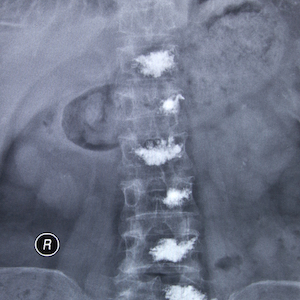

In this case, the doctor injects a bone cement mixture of polymethylmethacrylate (the same cement used in joint replacement surgery), barium or tantalum powder (makes the cement visible on X-ray), an antibiotic, and a solvent into the vertebral body. The cement will harden, strengthen and stabilize the vertebra, and prevent further collapse. In addition to relieving pain, those vertebrae that are weakened but not yet fractured, can be strengthened, thus preventing future problems. Most patients report pain relief within 24 to 72 hours and between 70% and 80% has sustained pain relief.

This will cause a burning sensation for a few seconds. A special bone needle is inserted into the vertebral body. With the assistance of a special X-ray machine called a fluoroscope, the doctor injects a radiopaque dye (contrast solution) to verify location of the needle. When the needle is in the correct position, the doctor will inject the cement mixture. During this time, you will not feel pain but you may feel some pressure. After the procedure, you will continue lying on your stomach for an hour or two. We ask that you remain at the Clinic until the doctor feels you are ready to leave.